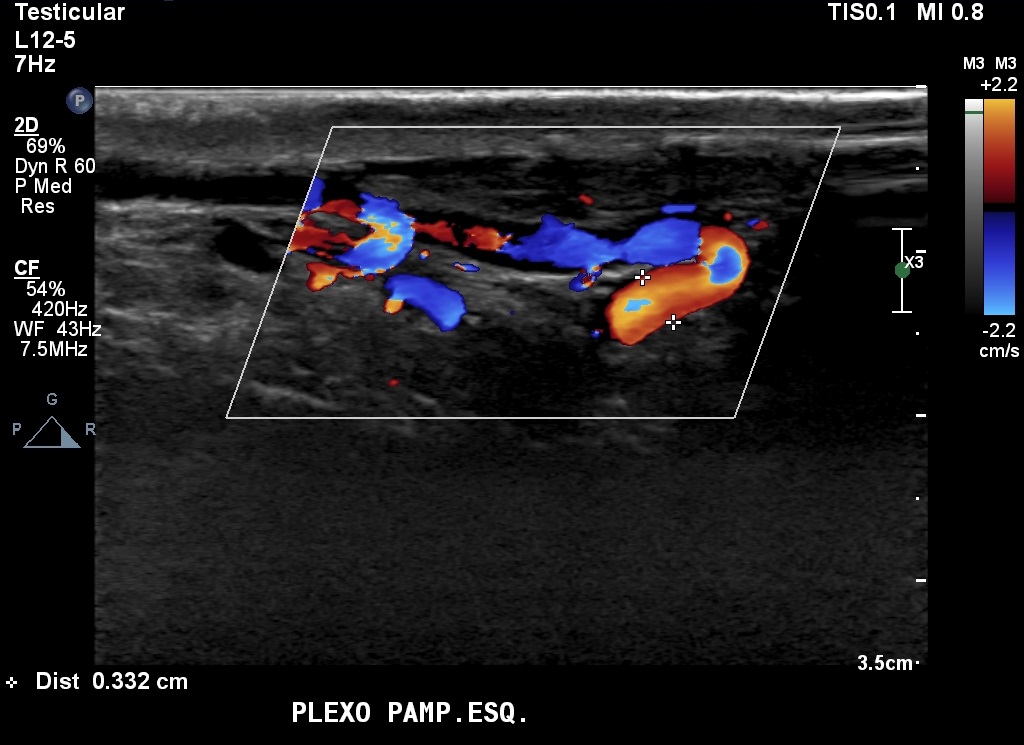

Adolescente de 16 anos veio ao laboratório para fazer ultrassonografia abdominal e escrotal, embora não tivesse queixas clínicas ou alterações evidentes ao exame físico. Estava em acompanhamento laboratorial de proteinúria leve e albuminúria havia seis anos, sem causa esclarecida. Os valores de proteinúria variavam entre 0,21 e 0,68 g/L (VN inferior a 0,05 g/L) e 0,16 e 1 g/24h (VN inferior a 0,15 g/24h). Já os de albuminúria variavam entre 32 e 545 g/24h (VN inferior a 0,15 g/24h). Os demais exames laboratoriais de sangue e urina encontravam-se dentro da normalidade.

As imagens da ultrassonografia abdominal avaliaram o rim esquerdo (A) e a veia renal esquerda no eixo longo (B). Ao estudo com Doppler colorido e pulsado, a veia renal esquerda foi visualizada ao longo do seu trajeto (C) e as velocidades, aferidas na sua porção proximal (D). A ultrassonografia escrotal com Doppler, em repouso, mostrou o fluxo das veias do plexo pampiniforme esquerdo (E)